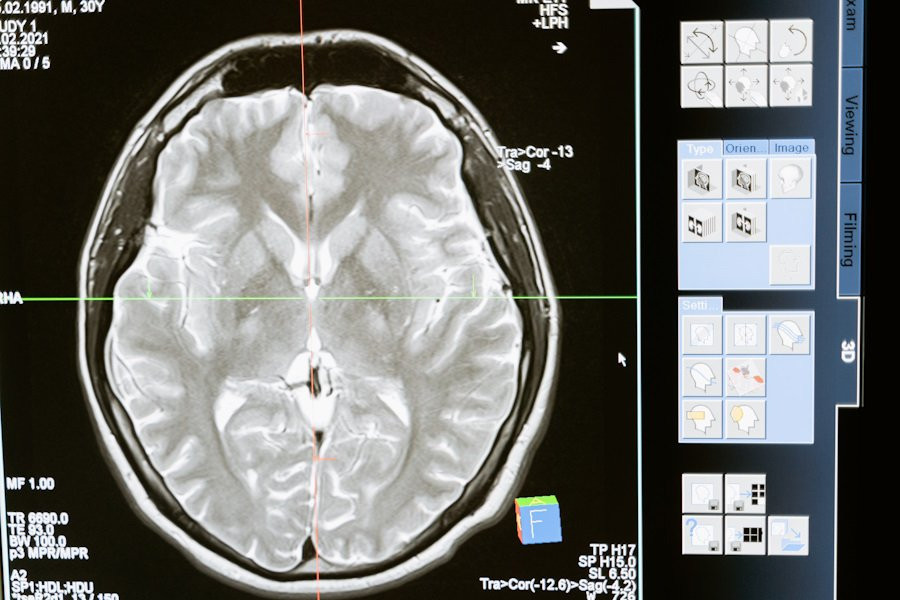

Исследователи из Kyushu University (Япония) сделали важный шаг в лечении рассеянного склероза (РС), серьезного заболевания, поражающего центральную нервную систему. В исследовании, опубликованном на портале Scientific Reports, команда выявила новую терапевтическую цель для лечения РС на поздних стадиях.

Ученые обнаружили, что белок Cx43 играет ключевую роль в развитии рассеянного склероза. В хронических стадиях заболевания, а также в его животной модели — экспериментальном аутоиммунном энцефалите (EAE) — наблюдается повышенное выражение Cx43 из-за увеличения количества специфических клеток, называемых астроглиями.